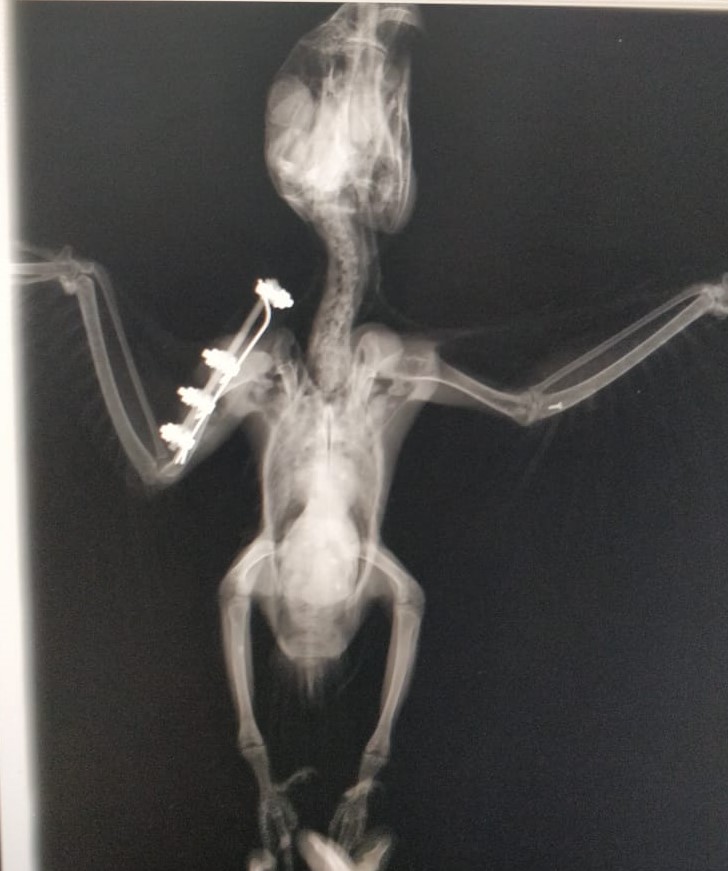

“Assim que constatamos a fratura em asa, o animal passou por um processo de estabilização com bandagem e ficou no aguardo do procedimento cirúrgico. Entramos em contato com a Clínica Dupet, que prontamente aceitou a parceria, e, assim, conseguimos marcar uma cirurgia de Osteossíntese de Úmero, com a parceria do Dr. Plínio Montalvani. Graças à eficiência de toda a equipe que participou, o procedimento cirúrgico na arara-azul-de-lear foi um sucesso”, explica Márcio, que também é médico veterinário do Inema.